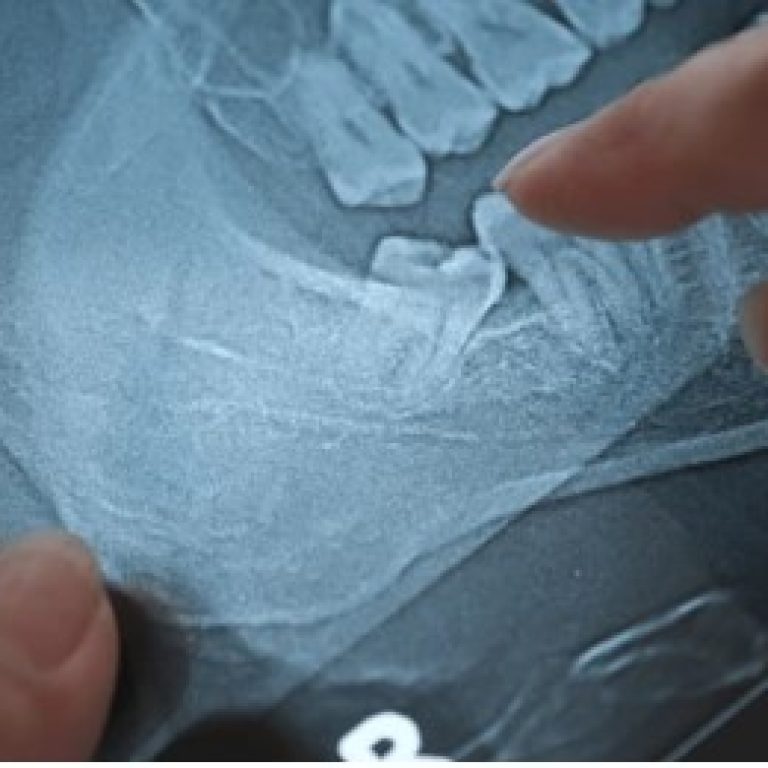

Unnecessary root canal treatments (RCTs) can occur in dental practices worldwide, including in Bangladesh, due to factors like …